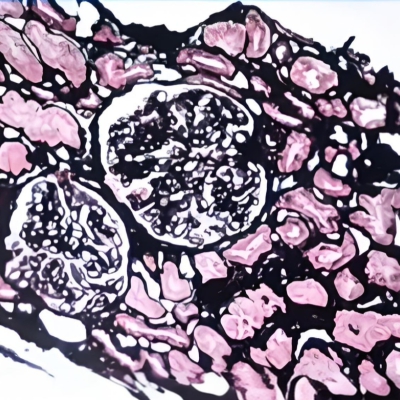

天狼猩红染色(胶原纤维定性)

¥25元/样

892